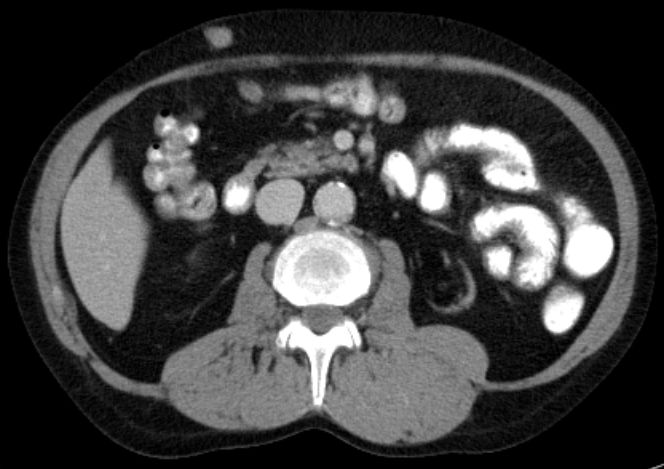

| Metastasierung | 65-jähriger Mann mit primär metastasiertem Merkelzelltumor.

Metastase in der Bauchdecke.![]() |

Metastase ventral der Transplantatniere.![]() | ||